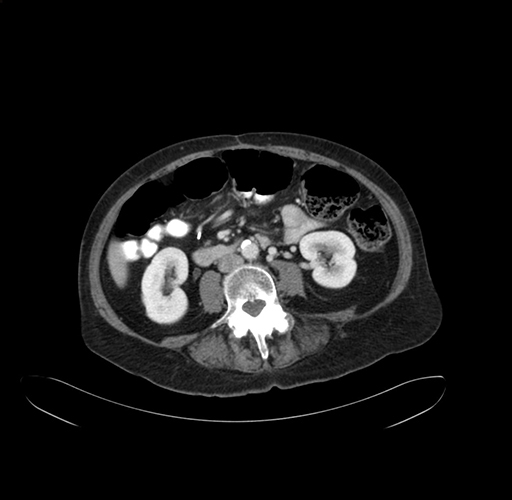

Pre-Chemo: Axial Venous

Axial Venous